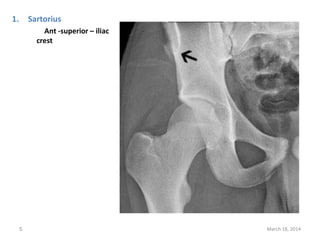

The document lists 10 common sites of avulsion fractures caused by the tearing away of tendons or ligaments from bone. It identifies the specific muscles or tendons that can cause avulsion fractures at the iliac crest, ischial tuberosity, greater trochanter, lesser trochanter, posterior calcaneus, olecranon process, superior patella, inferior patella, and tibial tuberosity.